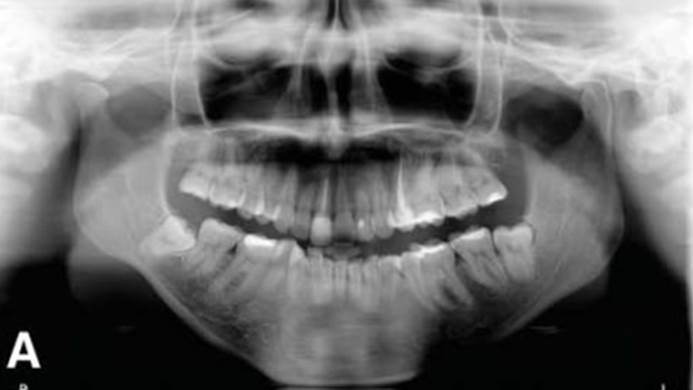

Clinical case: Bone growth in deepest thread of 8.0mm AnyRidge fixture

- Courtesy of Dr. Kwang Bum Park -

Clinical case: Bone filling into the bottom of deepest thread at 8.0mm AnyRidge fixture

Keywords

AnyRidge, Knifethread ,extraction socket, ,initial stability ,Allograft, ,osseointegratio ,Dr. Kwang Bum Park, , Mandibular, Single replacement, AnyRidge, Mega-oss,

Products used

Implant system-AnyRidge, Regeneration-Mega-Oss